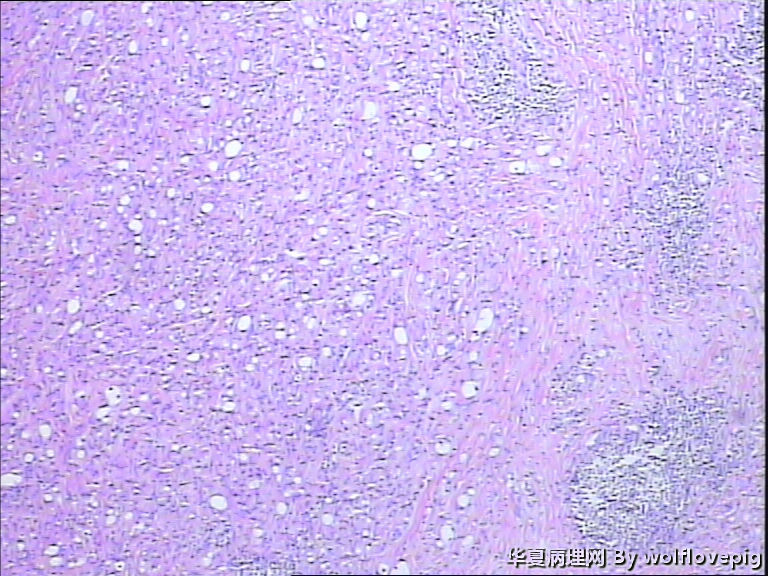

男,60y,左阴囊包块6月,位于附睾尾与睾丸之间,无粘连。灰白结节一个0.7*0.3*0.3,切面灰白、实体 、质韧。

图4

典型的腺瘤样瘤

同意腺瘤样瘤